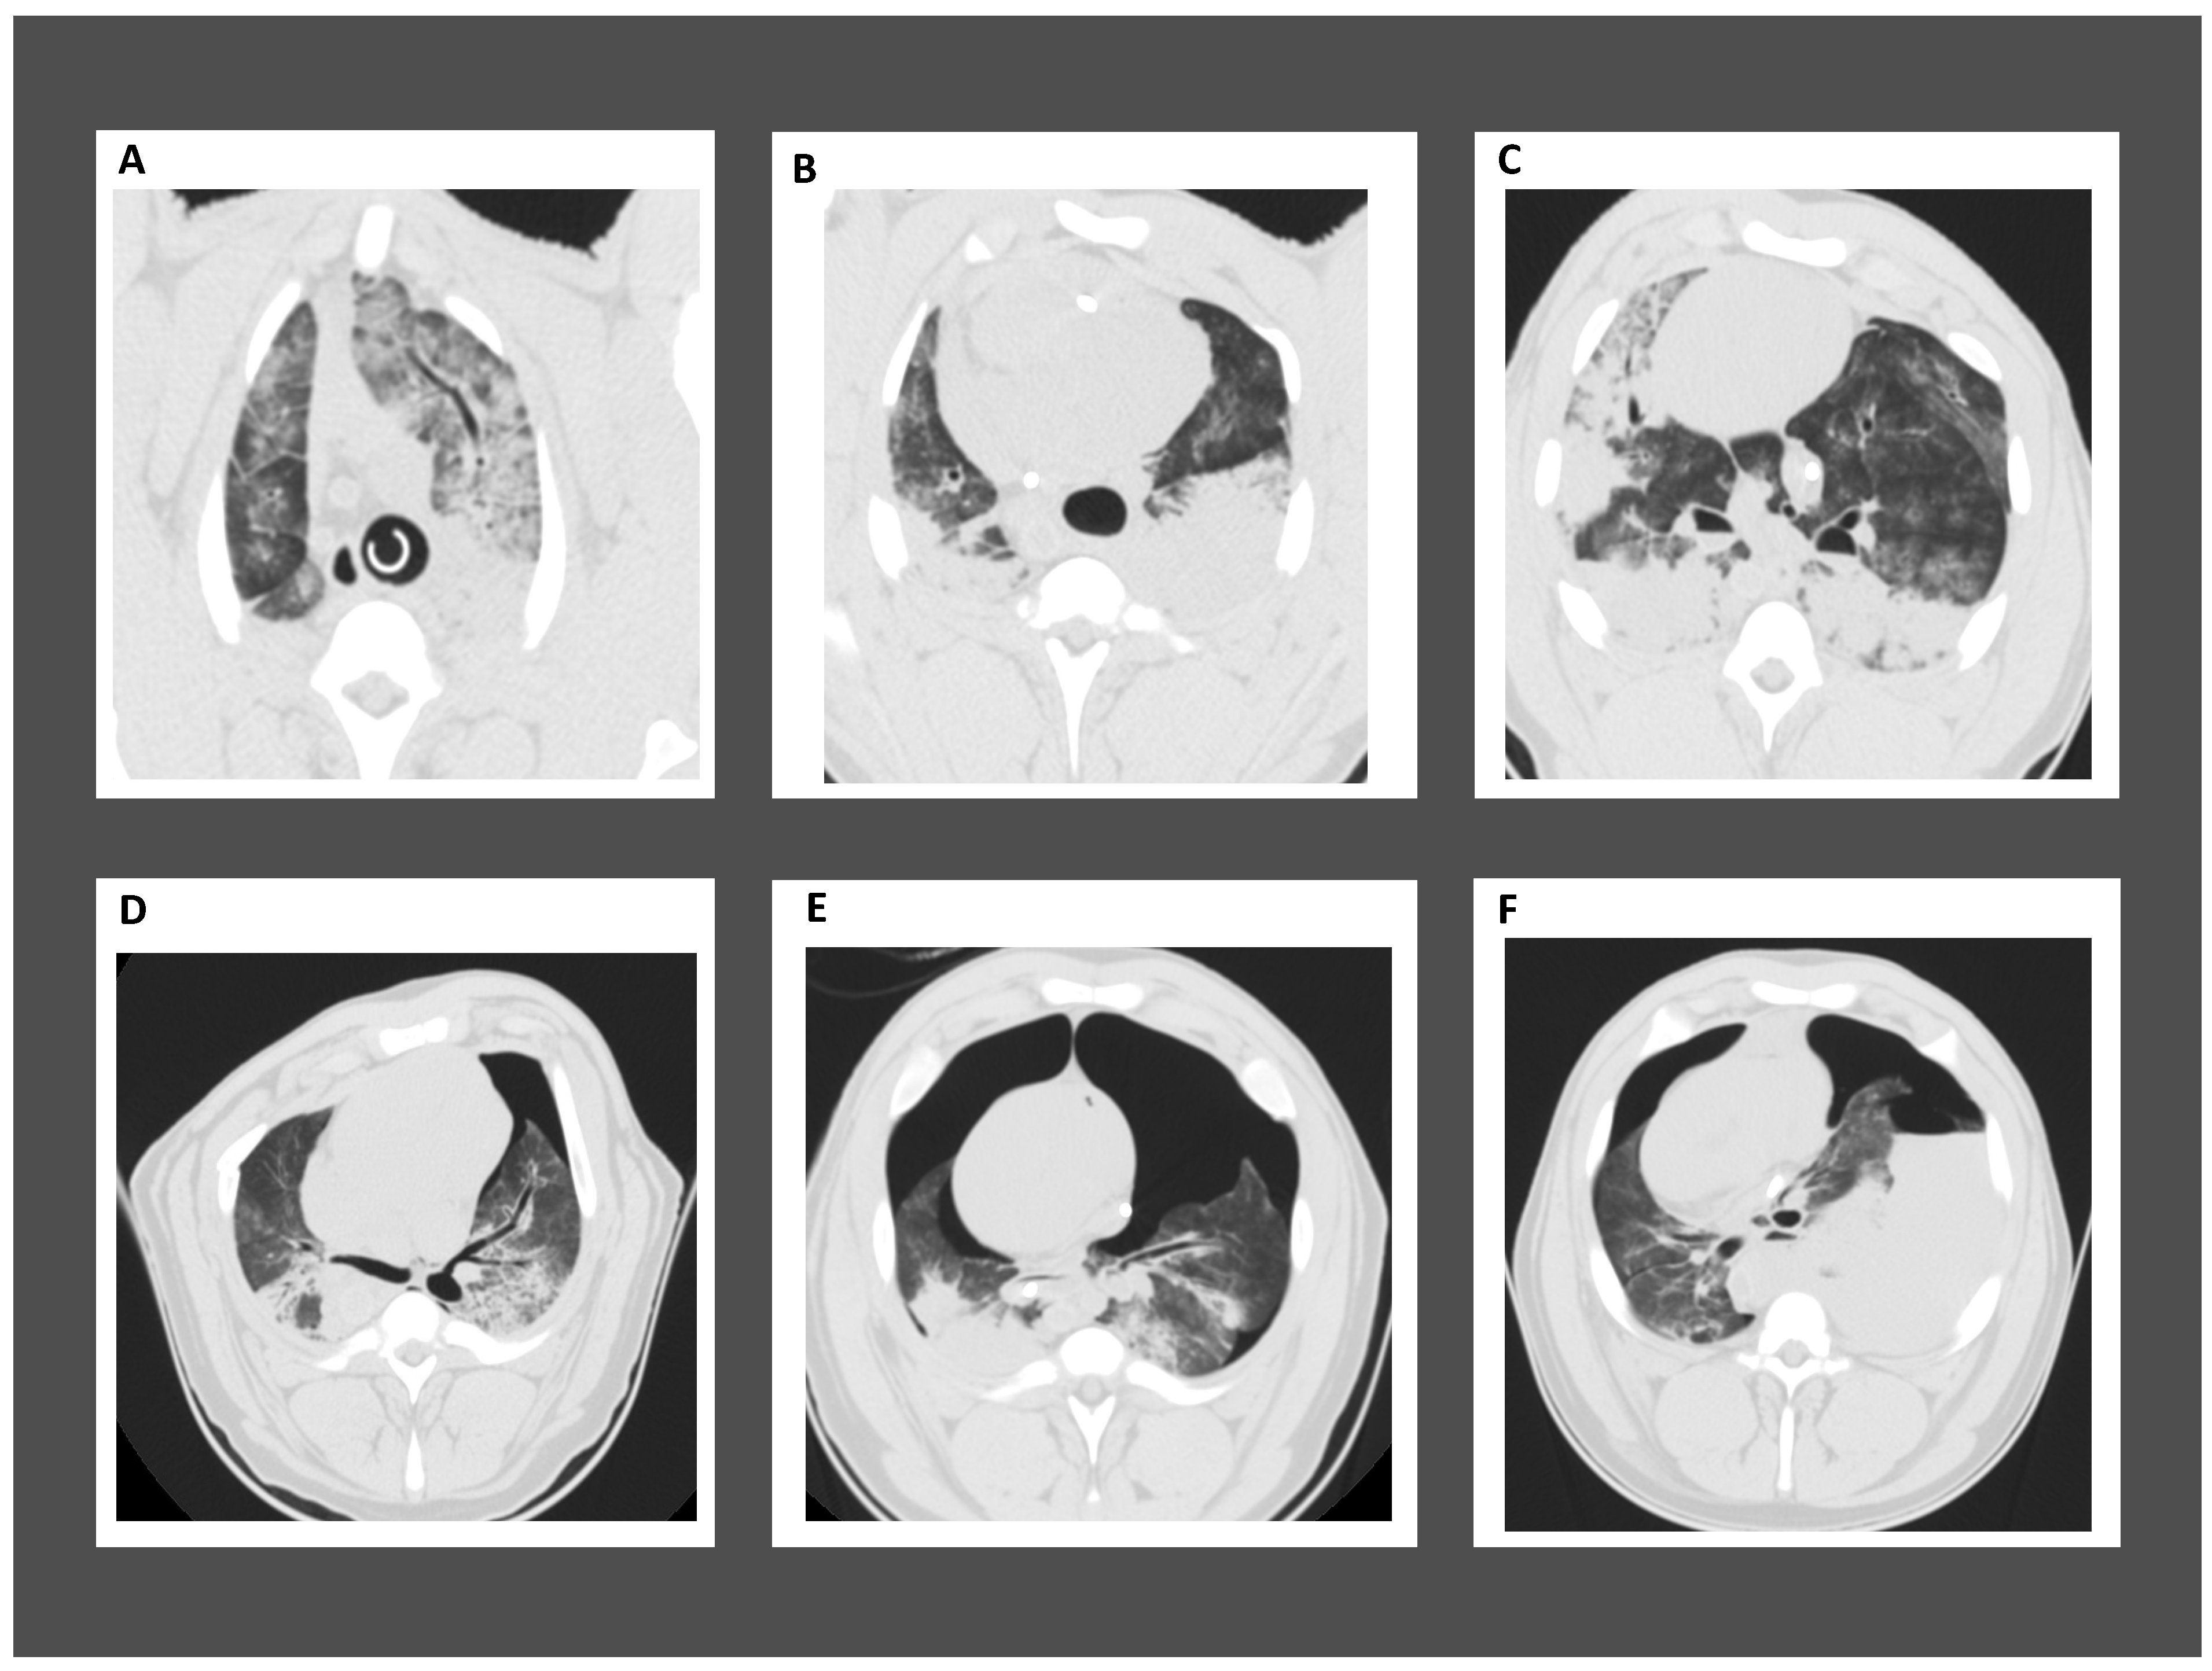

3. ALI in Post-Cardiac Arrest Patients

4. Cardiopulmonary Resuscitation-Associated Lung Edema (CRALE)